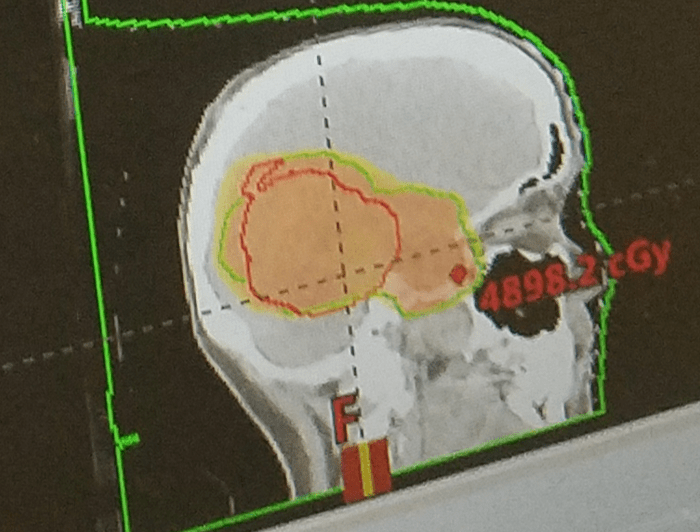

Say hello to my dose cloud. I believe the red outline is A-A-ron’s cavity, where he is no more. The green outline around that is where there is healthy brain that needs to be protected. The red shading is where the radiation is targeted. That must mean that A-A-Ron’s remainder sits between the red line and the green line near that red dot in the lower right of the cloud…which would make sense considering they took out 80% of him. They radiate the cavity in case there are microscopic cancerous cells in there that might grow in the future. The place where the red and green outlines cross is an example of doctors making trade-offs to get as much of the cancerous cells as possible while saving as much of the healthy brain cells as possible. I assume that any shading outside the green line is more of that. More things I never expected to learn in my life!

Successful first week of radiation and chemo with minimal side effects. 5 more weeks to go!